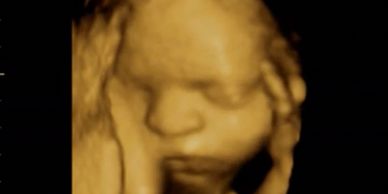

Llevamos control prenatal con programa de atención del parto y cesárea. Realizamos ultrasonidos obstetricos 2D, 3D y 4D. Visitanos en la 9 avenida 2-59 zona 1, dentro del Hospital Permanencia Mèdica. Preguntar por las doctoras Ana González . Llamanos al 2220-0083.

Realizamos ultrasonidos obstétricos 3D y 4D, el precio del ultrasonido 4D es de Q340.